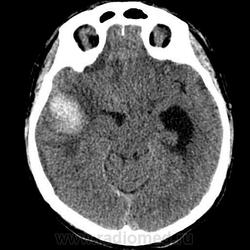

Я конечно никогда не работал на КТ и не описывал КТ снимки, но могу предположить, что имеется:

1. Оболочечная (субдуральная) гематома левой гемисферы мозга /гиподенсная, но выше чем ликвор в желудочках + значительный масс-эффект в виде сужения субарахноидальных пространств и борозд , деформации желудочковой системы и дислокации срединных структур/, явно не острая, может подострая.

2. Внутримозгая гематома (гиперденсная - значит острая стадия) в левой височной доле с наличием выраженного перифокального вазогенного отека и значительного масс-эффекта.

Согласен с предыдущим описанием. Внутримозговая гематома (острая), хроническая субдуральная гематома (скорее всего), надо смотреть по плотности, смещение срединных структур и сдавление желудочковой системы справа. Можно предположить разрыв АВМ. Контрастирование не проводили?

Прооперирован, сидит, разговаривает, ничего не помнит о том, как получил травму. Всё правильно, я тоже написала о субдуральной гематоме, объём 110 мл. Учитывая несколько гиперденсных участков в лобной части гематомы, вероятно, имело место повторная травма. Плотность гематомы преимущественно 25 ед.Н. Компрессия конвекситалов правой гемисферы субдуральной гематомой. Внутримозговая гематома 70 ед.Н в правой височной доле с перифокальным отёком, зона ушиба в правой лобной доле. Латеральная дислокация 2 см, выраженная, аксиальная дислокация. Асимметрия желудочков, выраженное смещение и деформация. Контрастирования не было.